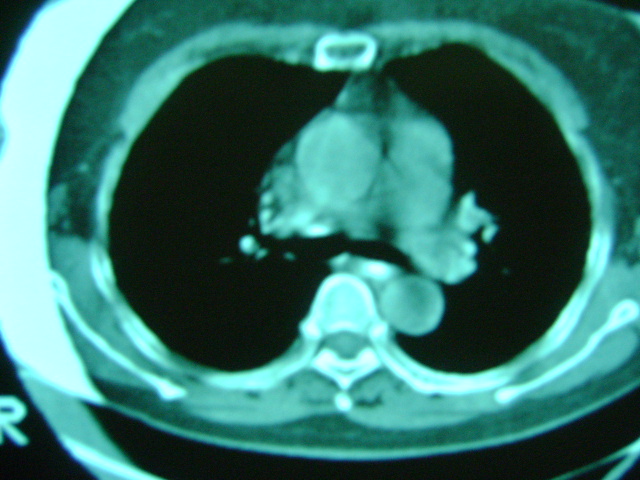

朋友的母亲,56y,咳嗽三个月,感觉左肺门不对,请大家给点意见

心功能不全肺淤血

老年人,肺动脉略迂曲